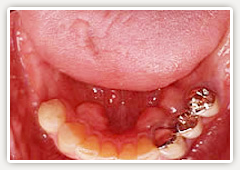

【術前】

4~5年前より左右奥歯に義歯を使われていますが、留め金が舌に触ったり、がたついて食べ物が美味しく無いそうです。また義歯そのものをつけていることが煩わしいそうです。